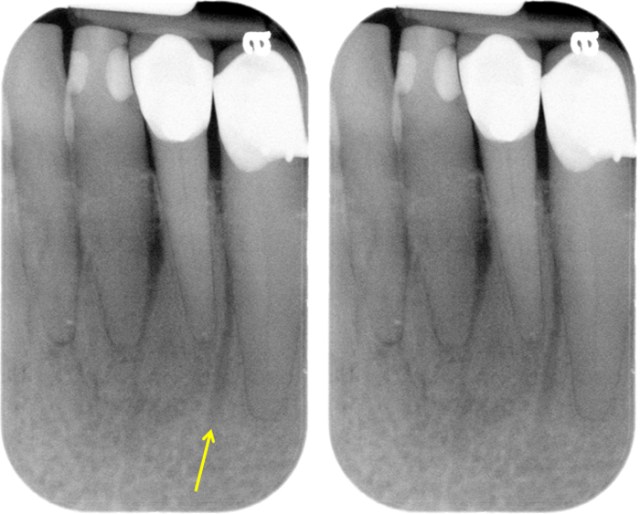

Mandibular canal

Pathway in the bone where the inferior alveolar nerve and blood vessels flow through the mandible.

Extend from mandibular foramen within the ramus to the mental foramen.

Appears radiopaque